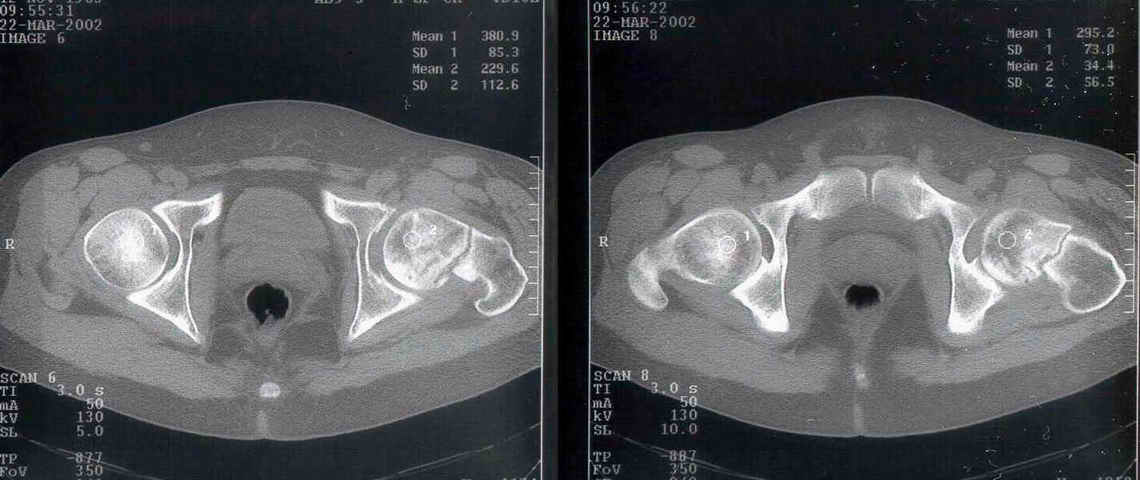

Уважаемый Александр! По 38-летнему пациенту. На томограмме имеются явные признаки асептического некроза. Этот процесс будет развиваться стремительно.

1-2 года и Вы вынуждены будете эндопротезировать пациента. Есть ли необходимость в дополнительной операции (остеотомии)? У 35-летнего пациента

At first is necesary take a Magnetic Resonance for the diagnosis de avascular necrosis.

I see zones of osteoporosis in the head and for this is necesary a vascular existence, then for me was necesary the MR.

You have a non union neck, avascualr necrosis and varus deformity.

Inspite of the avascular necrosis it is still wothwhile to get the femur neck united.